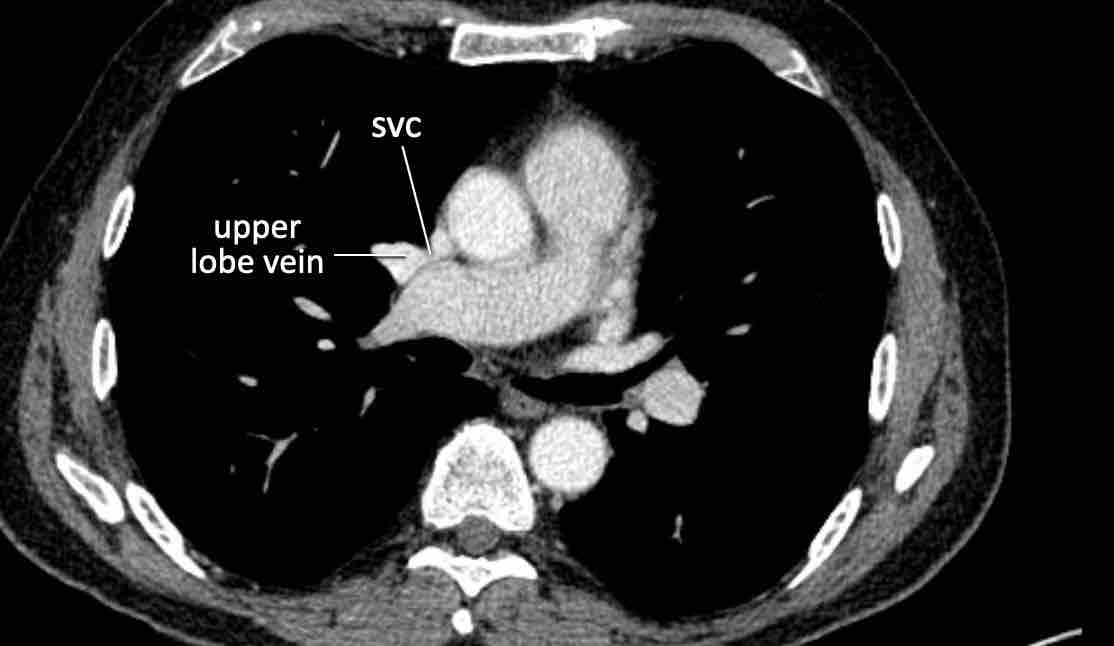

Trong PAPVR, thùy trên trái thường dẫn lưu vào tĩnh mạch tay đầu trái. Bất thường phổ biến tiếp theo là thùy trên phải dẫn lưu vào tĩnh mạch chủ trên.

PAPVR bên phải có mối liên quan chặt chẽ với thông liên nhĩ thể xoang tĩnh mạch (khoảng 40%), đây là một dạng thông liên nhĩ tại vị trí tiếp nối cavo-nhĩ. Do đó, cần kiểm tra sự hiện diện của dạng thông liên nhĩ này khi phát hiện PAPVR bên phải.

Hình ảnh

Bệnh nhân này được lên kế hoạch cắt thùy trên phải do ung thư phổi và bất thường mạch máu này ban đầu đã bị bỏ sót trên hình ảnh CT.

Những hệ quả trong phẫu thuật của bất thường như vậy nhấn mạnh tầm quan trọng của việc không bỏ sót các biến thể này.